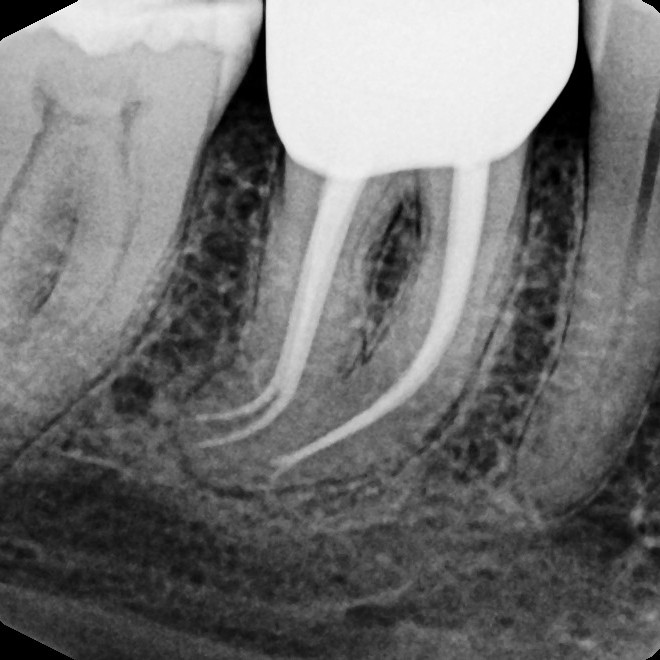

Before & After